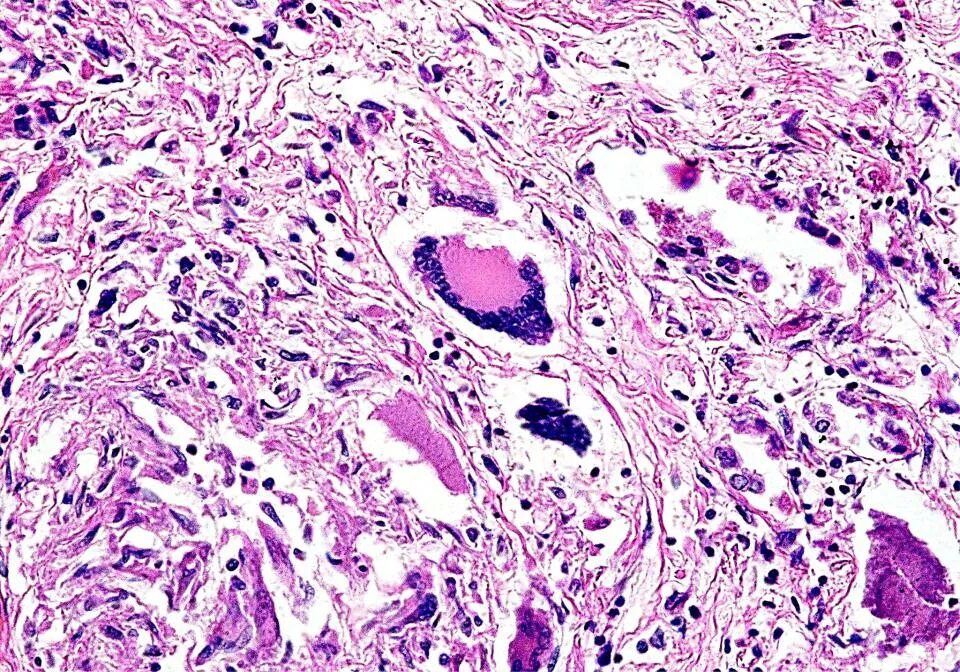

Гранулематоз лечение